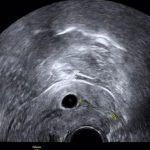

2012年8月再次怀孕了,在停经41天时出现了阴道少量出血,浅红色,9月28日检查B超提示右侧附件区非均质包块,异位妊娠待排,刘女士也只能无奈的接受手术。

4月4日刘女士找到了北京安太医院杨院长,通过询问病史得知刘女士怀孕了,可仍然是宫外孕,听说安太可以宫内转移术慕名而来!4月5日杨院长为刘女士在腹腔镜下进行了宫外孕宫内转移术,现术后已经20天,检查B超提示宫内早孕活胎!